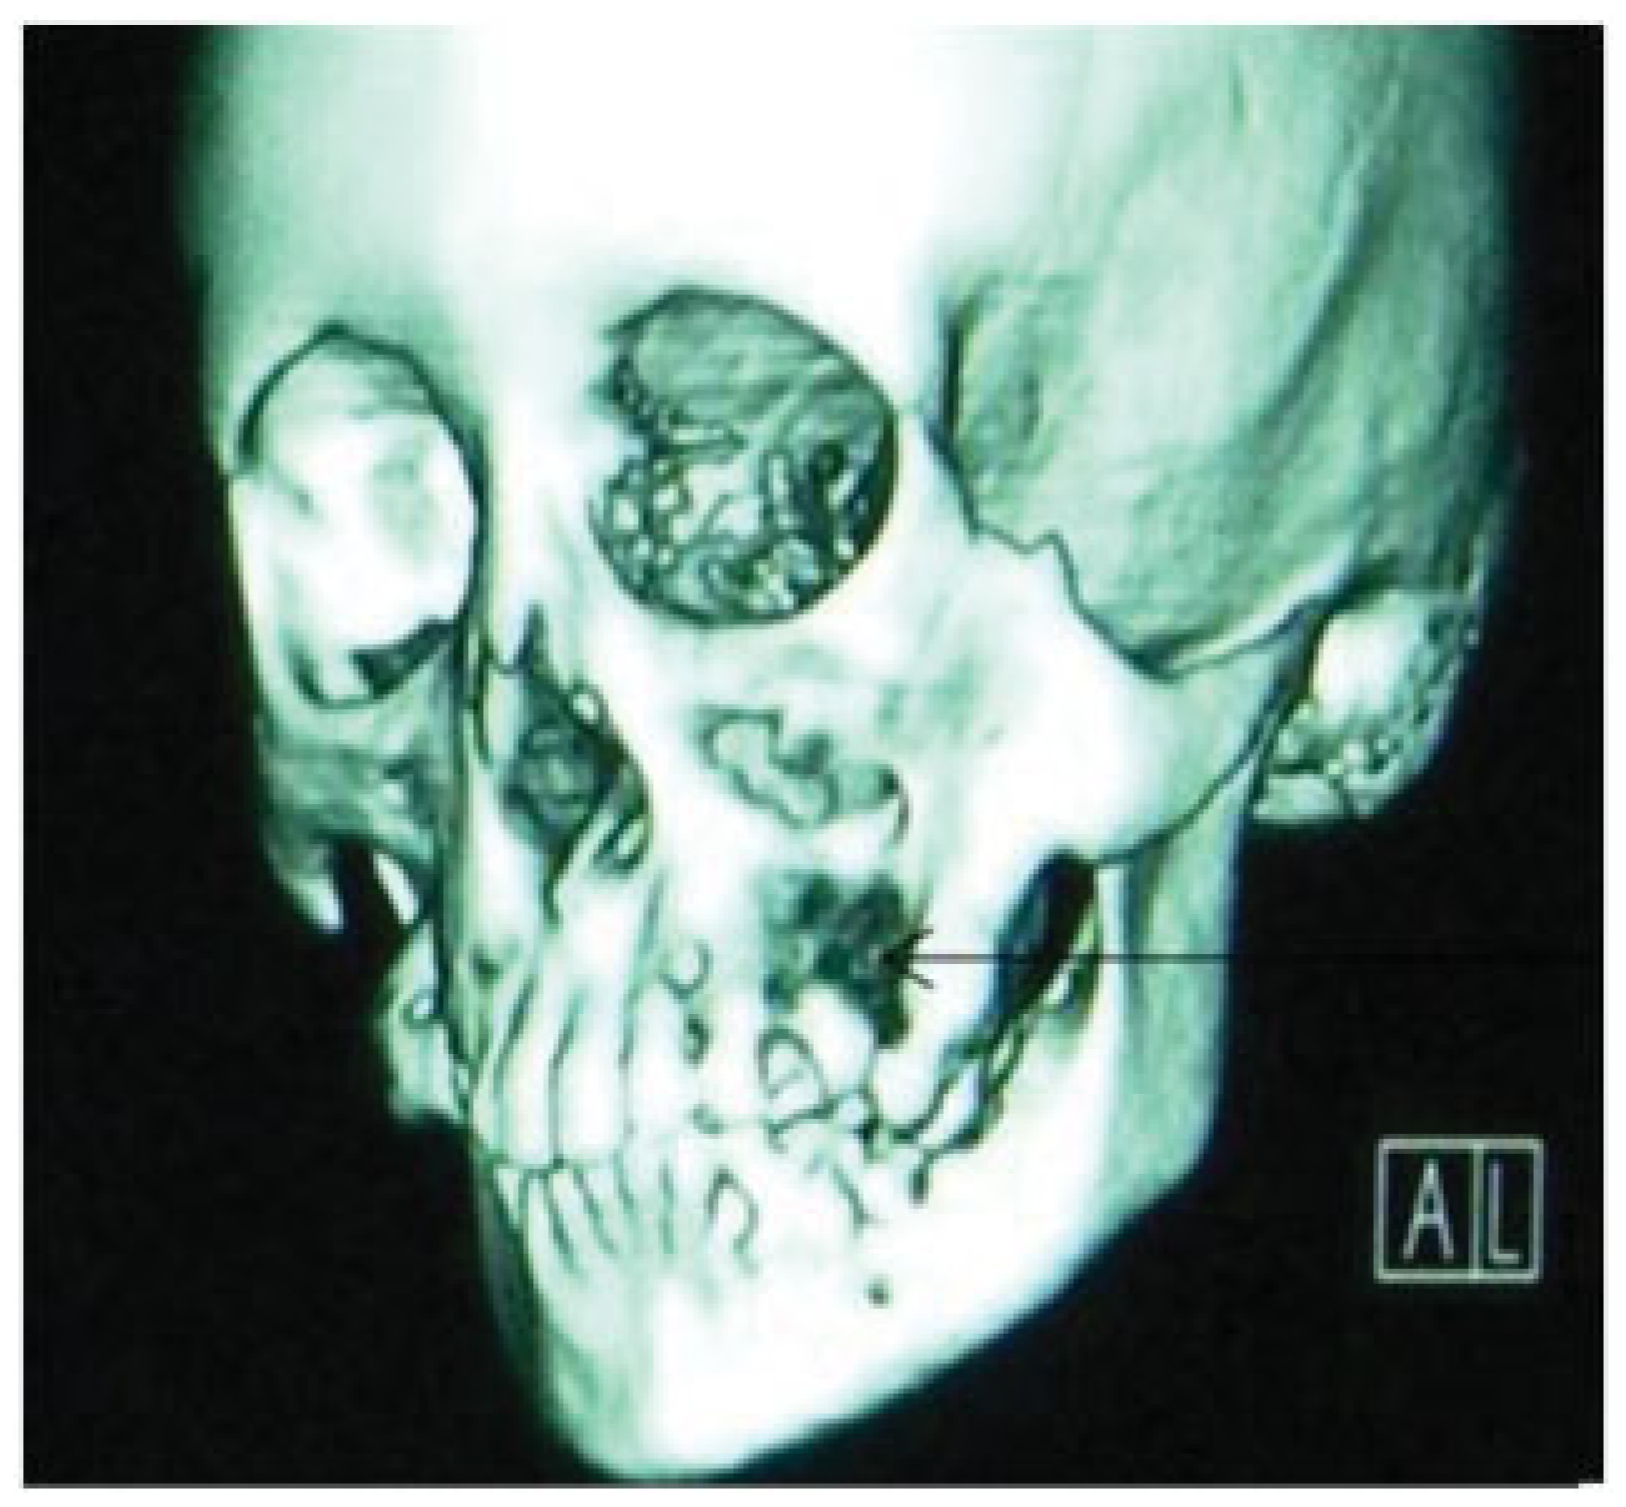

- Incomplete Tessier 7 soft tissue facial cleft and a complete skeletal Tessier 7 cleft on the right side

- Incomplete Tessier 5 skeletal and soft tissue Tessier 6 facial cleft on the left side